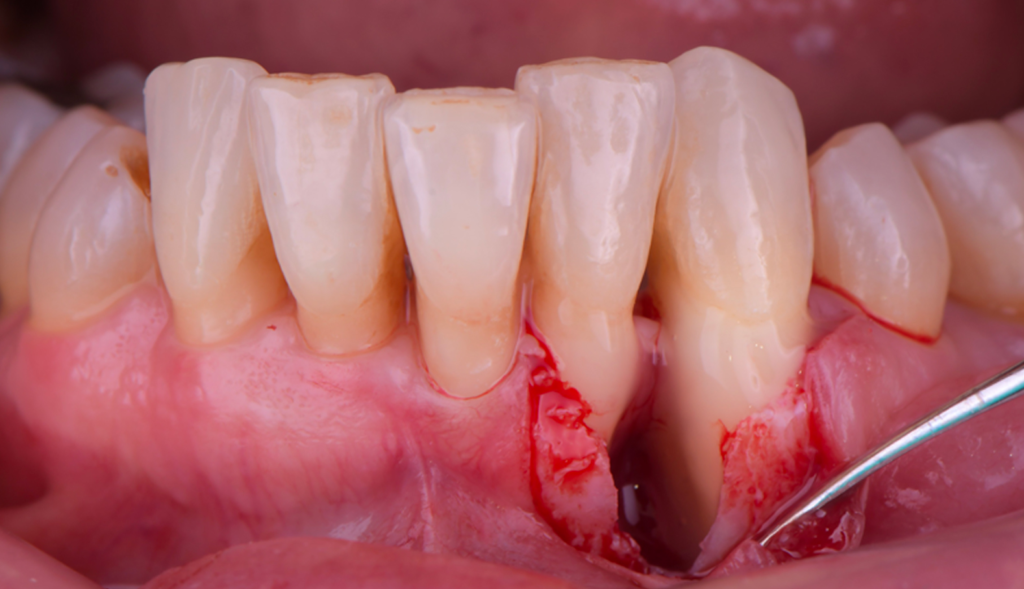

Lambeau d’Épaisseur Totale

Facteur clé : La rapidité de la cicatrisation dépend de l’épaisseur du caillot.

Chronologie :

3ème et 4ème jour : La résorption du caillot commence

6ème et 7ème jour : Le caillot laisse la place au tissu de granulation, qui sera progressivement remplacé par du tissu conjonctif

2ème et 3ème semaine : Phénomène de résorption osseuse et apposition tissulaire concomitante

3 semaines : Les ostéoblastes sont présents et la formation osseuse commence

Entre 4ème et 5ème semaine (40 jours) : Phases de maturation et de réparation complète

Important : Le lambeau d’épaisseur totale entraîne toujours une certaine résorption osseuse par dénudation du périoste.

Lambeau d’Épaisseur Partielle

Avantage majeur : Le phénomène de résorption-apposition existe, mais dans ce cas il y a une certaine économie osseuse au cours de la cicatrisation grâce à la préservation du périoste.

Chronologie modifiée :

4ème jour : La résorption osseuse commence plus tôt (car le tissu conjonctif laissé en place est plus rapidement vascularisé)

Jusqu’à la fin de la 2ème semaine (15 jours) : La résorption se poursuit mais reste limitée

Conclusion : L’économie osseuse est significative par rapport au lambeau d’épaisseur totale, faisant du lambeau d’épaisseur partielle un choix préférentiel dans de nombreuses situations cliniques.